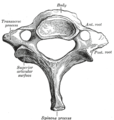

寰椎C1,是最起始的脊椎骨,与枢椎一起构成连接头颅与脊柱的关节连接。它的主要特点是它没有椎体,因为寰椎的椎体与枢椎椎体相融合。

枢椎C2,构成寰椎旋转的轴心。枢椎最显著的特征是垂直于身体表面向上的坚固的齿状突(齿突)。椎体前部比后部深,并向前向下延伸,以便与第三椎骨的前上部重叠。